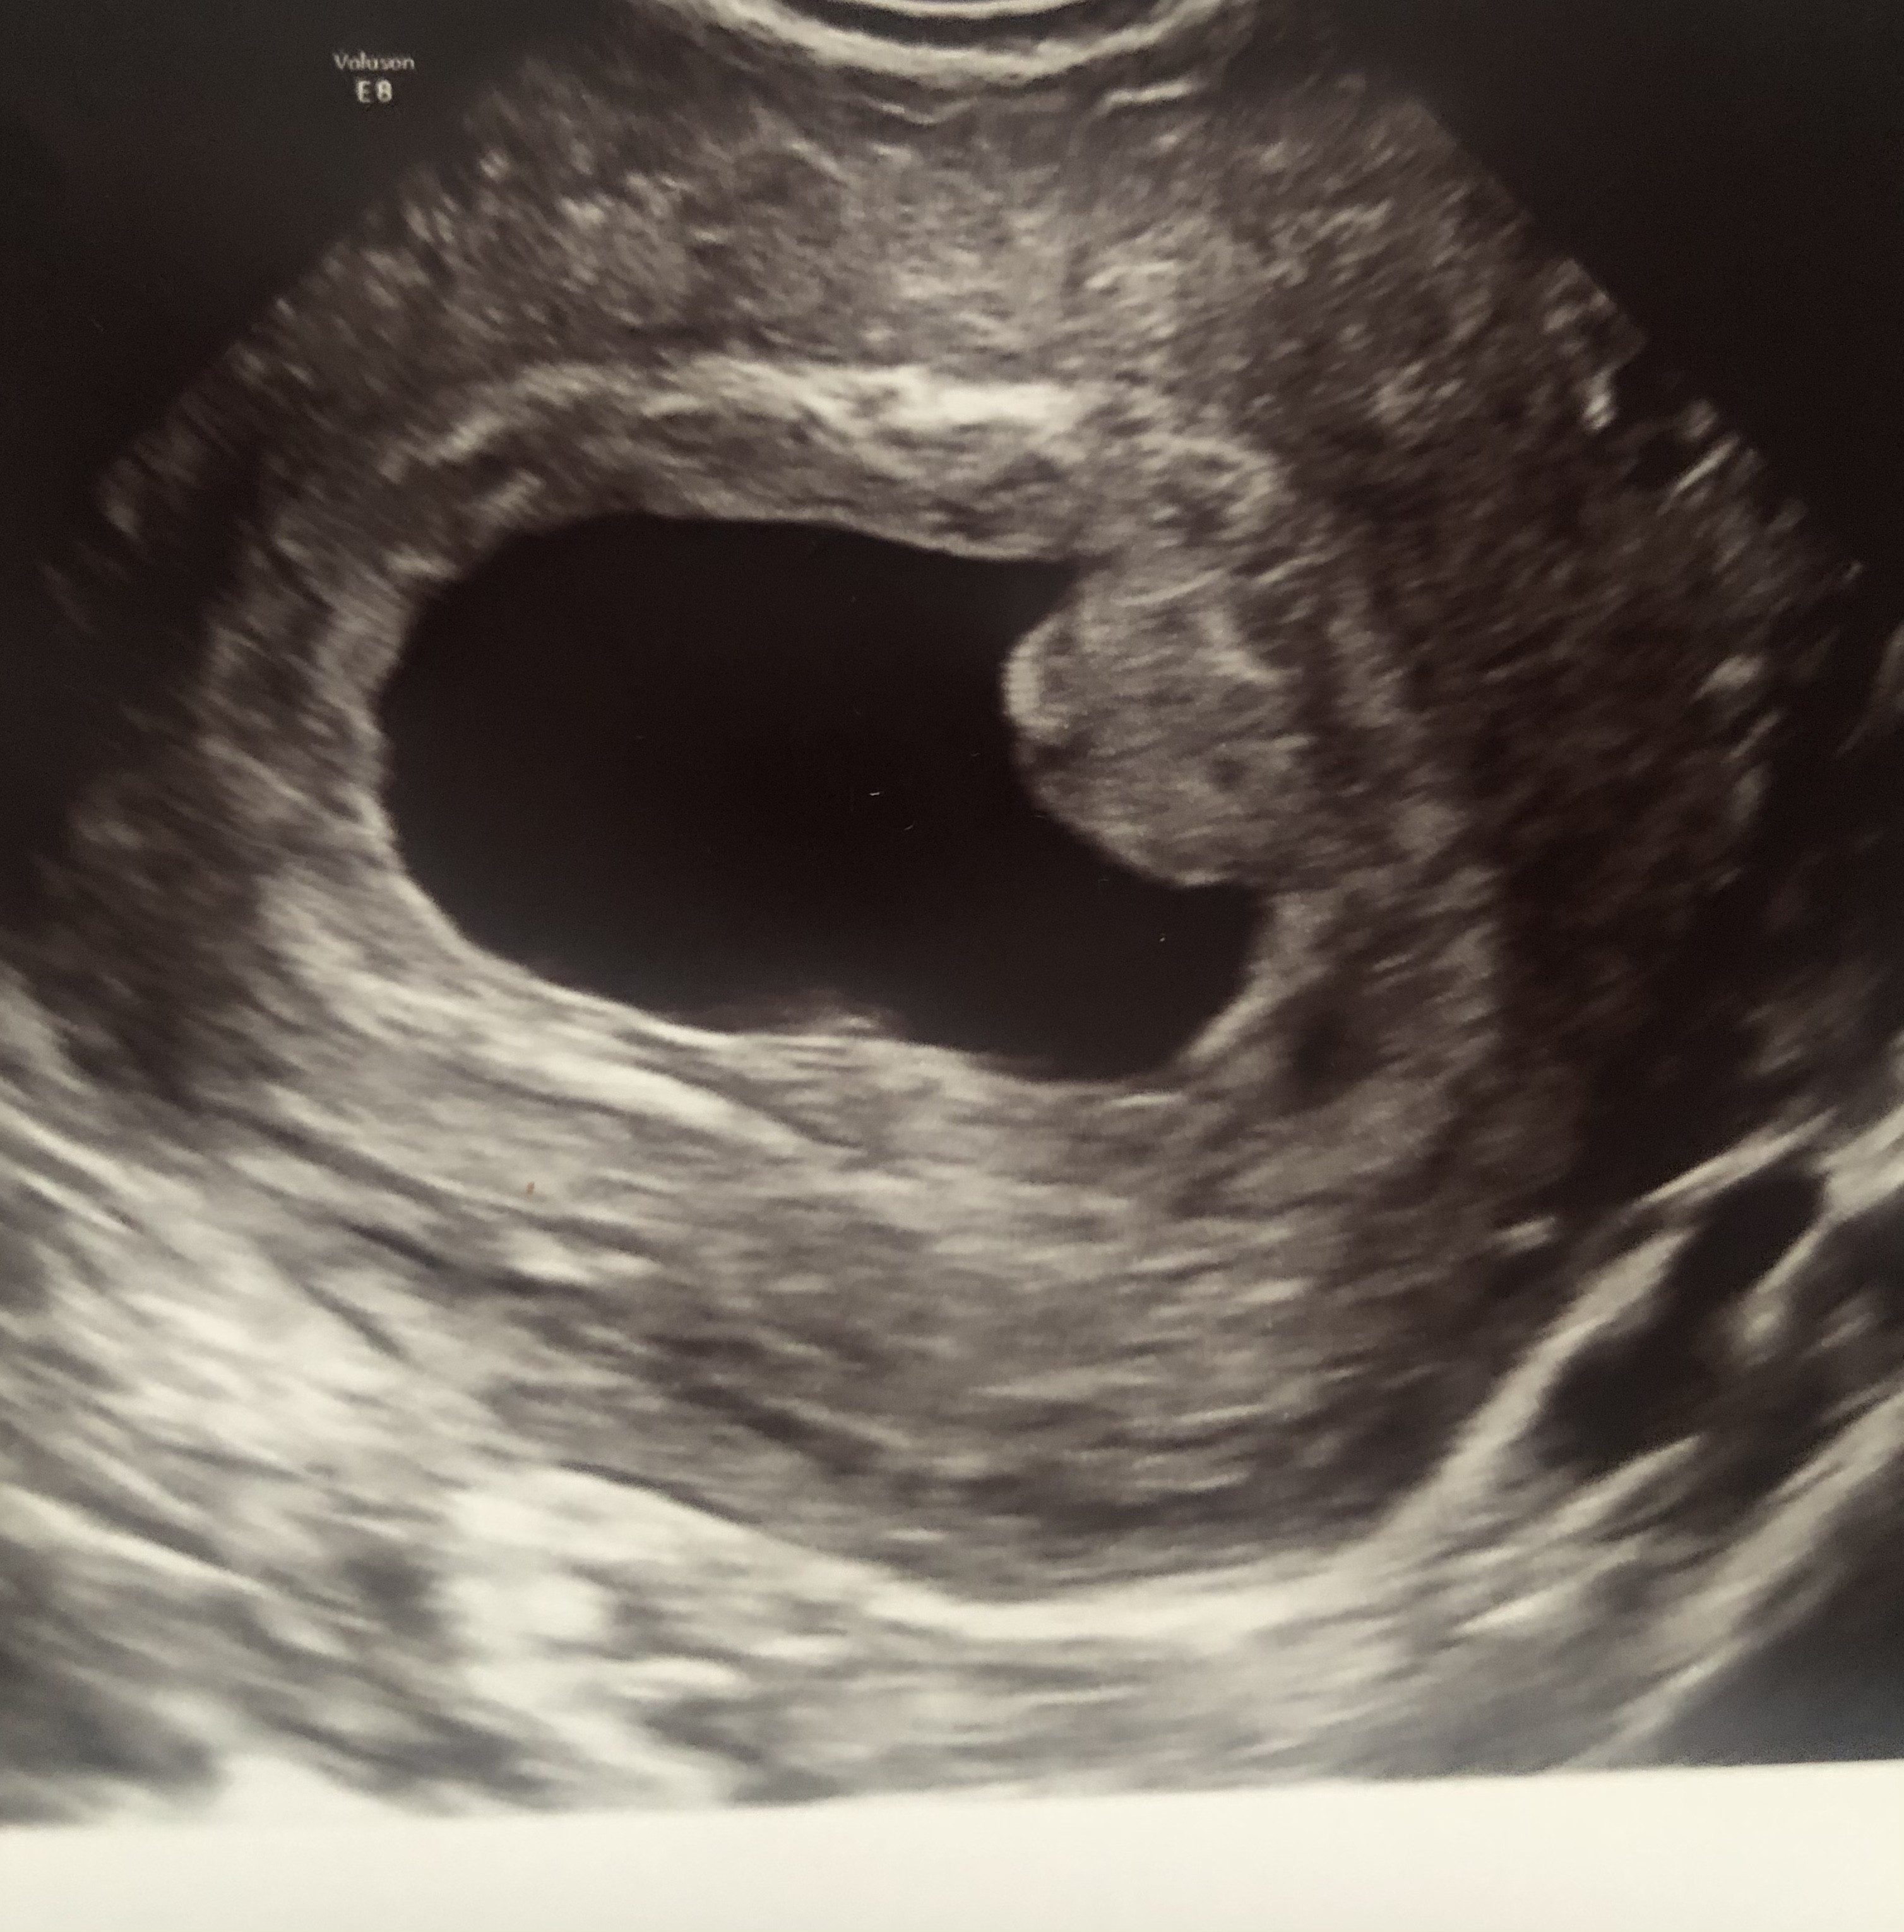

Nieobecna akcja serca w 6 tygodniu

Dziewczyny pomóżcie, czy coś z tego jeszcze będzie? CRL 94 mm ale brak widocznego serca. Wychodzi 7 tydzień ciąży. Za tydzień mam powtórzyć usg, jak nie to szpital. Czy ten zarodek nie wyglada dziwnie???